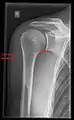

Imaging

Imaging of the shoulder includes ultrasound, X-ray and MRI, and is guided by the suspected diagnosis and presenting symptoms.

Conventional x-rays and ultrasonography are the primary tools used to confirm a diagnosis of injuries sustained to the rotator cuff. For extended clinical questions, imaging through Magnetic Resonance with or without intraarticular contrast agent is indicated.

Hodler et al. recommend starting scanning with conventional x-rays taken from at least two planes, since this method gives a wide first impression and even has the chance of exposing any frequent shoulder pathologies, i.e., decompensated rotator cuff tears, tendinitis calcarea, dislocations, fractures, usures, and/or osteophytes. Furthermore, x-rays are required for the planning of an optimal CT or MR image.[23]

X-ray

Projectional radiography views of the shoulder include:

- AP-projection 40° posterior oblique after Grashey

The body has to be rotated about 30 to 45 degrees towards the shoulder to be imaged, and the standing or sitting patient lets the arm hang. This method reveals the joint gap and the vertical alignment towards the socket.[24]

- Transaxillary projection

The arm should be abducted 80 to 100 degrees. This method reveals:[24]

- The horizontal alignment of the humerus head in respect to the socket and the lateral clavicle in respect to the acromion

- Lesions of the anterior and posterior socket border, or of the tuberculum minus

- The eventual non-closure of the acromial apophysis

- The coraco-humeral interval

- Y-projection

The lateral contour of the shoulder should be positioned in front of the film in a way that the longitudinal axis of the scapula continues parallel to the path of the rays. This method reveals:[24]

- The horizontal centralization of the humerus head and socket

- The osseous margins of the coraco-acromial arch and hence the supraspinatus outlet canal

- The shape of the acromion

This projection has a low tolerance for errors and, accordingly, needs proper execution.[24] The Y-projection can be traced back to Wijnblath’s 1933 published cavitas-en-face projection.[25]

CR. shoulay film.

Transaxillary conventional radiography

Y-projection conventional radiography